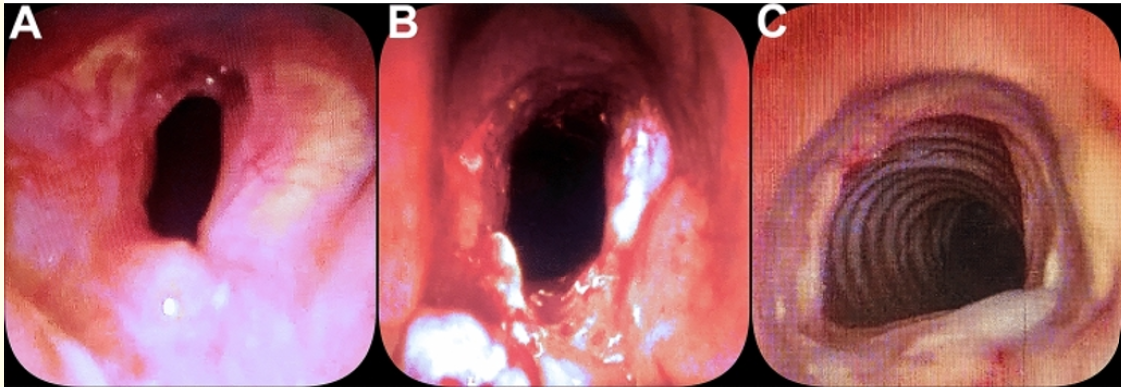

Post-Intubation Tracheal Stenosis in Non-Severe and Severe COVID-19 Patients